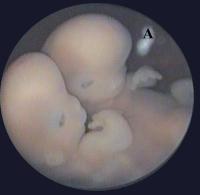

Abbildung 11: Embryoskopische Aufnahme eines Thorakopagus von 34 mm SSL, von rechts seitlich. Zwei separate Köpfe und eine ausgeprägte Verschmelzung am Thorax und im oberen Bereich des Abdomens, sind zu erkennen. (A) markiert Reste des Amnions (Karyotyp: 46,XX).

Keywords: GeburtshilfeSpeculumThorakopagus